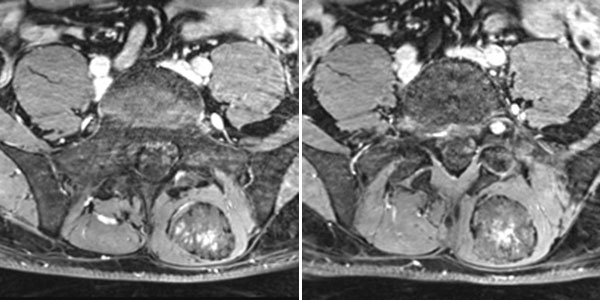

In der axialen T2-gewichteten Sequenz der MRT liegt die Läsion in der autochtonen Rückenmuskulatur. Klassischer Flüssigkeits-Flüssigkeits-Spiegel durch schwerkraftbedingte Sedimentationseffekte bei dem in Rückenlage ruhig im Gerät liegenden Patienten.

In der axialen, fettgesättigten T1-Wichtung nach Kontrastmittelgabe kommt es erst langsam und unvollständig zu einer zunächst inhomogenen Kontrastmittelanreicherung im Sinne eines Kontrastmittelpoolings. Auch dies ist relativ typisch für eine venöse Malformation.